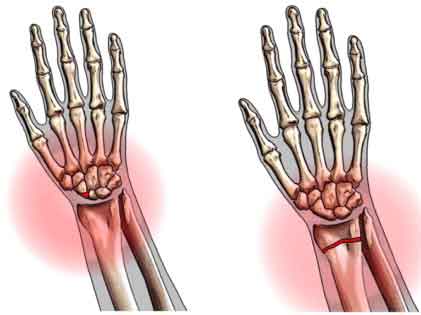

Bone Fracture And Healing System In Our Body